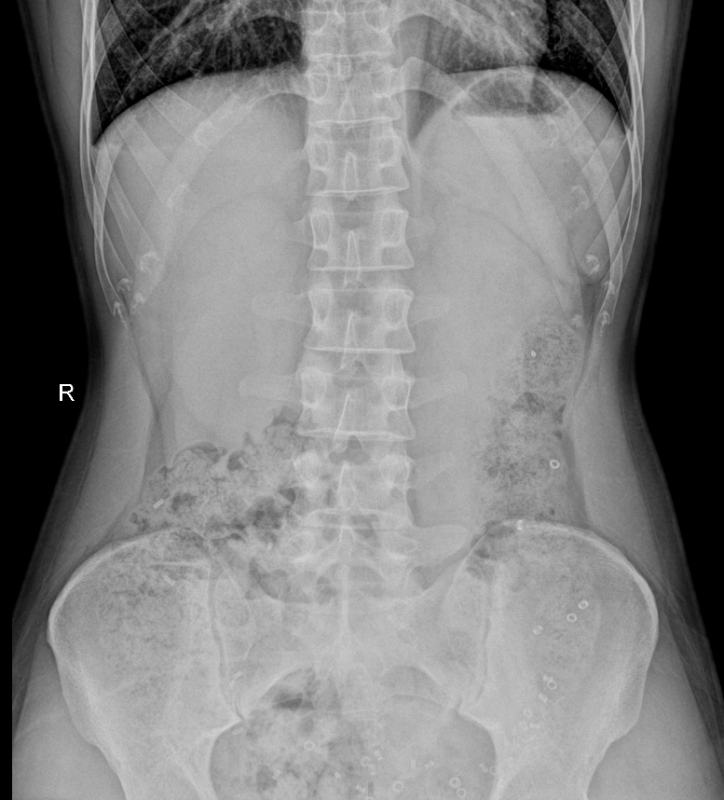

Xác định tỉ lệ rối loạn nhu động đại trực tràng bằng viên nang cản quang và một số yếu tố liên quan ở người bệnh táo bón tại Trung tâm Tiêu hóa – Gan mật, Bệnh viện Bạch Mai.